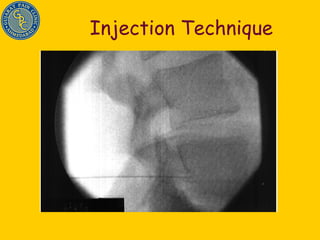

Injection Technique done with C-arm fluoroscopic device Steroid Reverses effect of inflammatory mediators Stops inflammation cascade Helps in healing annular tear Stabilizes cell membrane Delays pain impulse conduction Gives pan/ inflammation free time for disc herniation to settle down by natural process (Natural history of disc disease)

Injection Technique